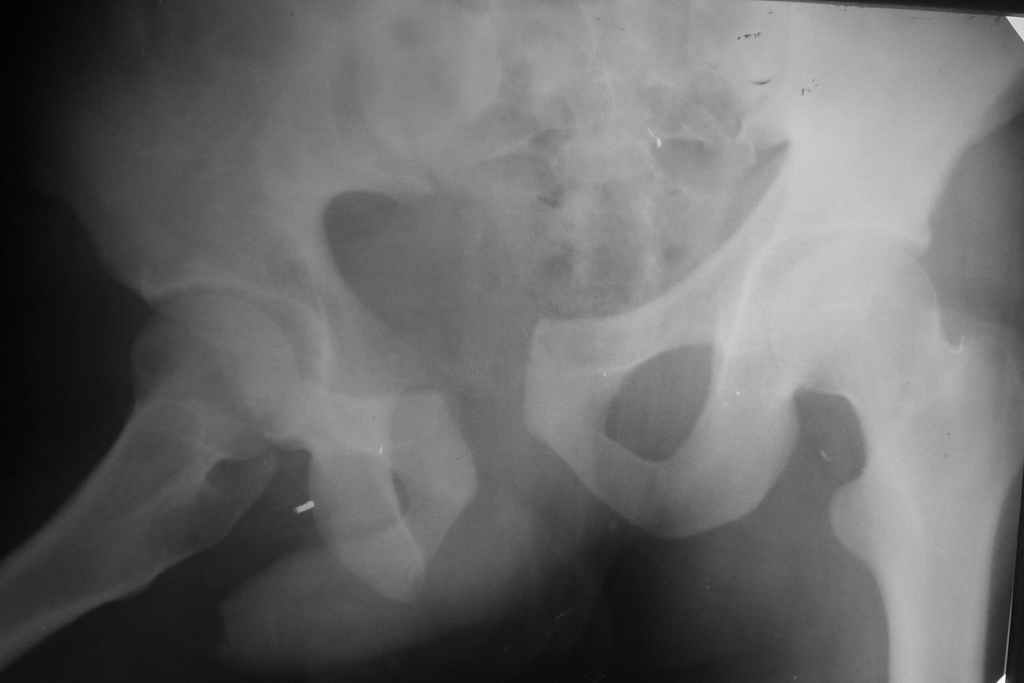

Уважаемые коллеги! Вчера оперировал больного с переломом таза месячной давности - разрыв симфиза, перелом обих ветвей лонной кости справа и трансфораминальный перелом крестца справа.

Виден разрыв правого крестцово-поздошного сочленения, разрыв симфиза.

Было пока только одно изображение - видимо, фас до операции.

Хотелось бы , конечно, увидеть картинки. Многие авторы считают, что остаточное смещение в задних отеделах не должно превышать 10 мм.